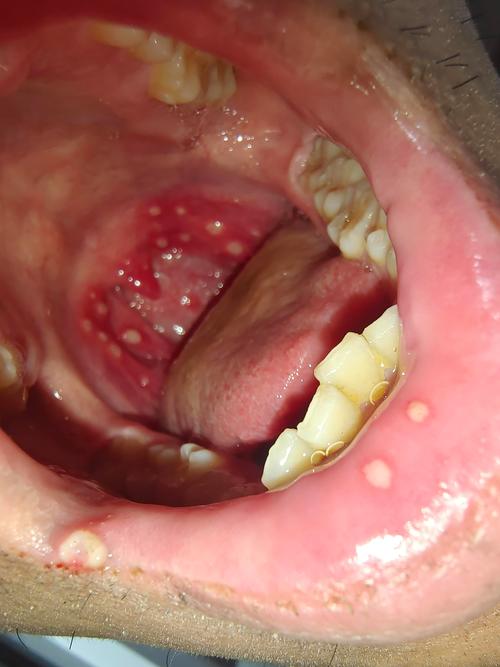

口腔溃疡白色假膜能强行挖掉吗?

千万不要自己用手或工具去挖掉口腔溃疡上的白色假膜!

加重疼痛和刺激:白色的假膜(医学上称为“纤维蛋白膜”)是溃疡表面的一层保护膜,它虽然看起来像“坏掉”的组织,但实际上是身体修复过程中形成的天然“创可贴”,强行挖掉会暴露下方娇嫩、暴露的溃疡面,就像撕开正在愈合的伤口一样,会立刻引起剧烈的疼痛,并刺激溃疡扩大。

延长愈合时间:这层假膜能隔绝唾液、食物、细菌等对溃疡的刺激,为溃疡的愈合提供一个相对洁净的环境,破坏了它,就等于破坏了愈合的“保护层”,新的组织更难生长,愈合速度反而会大大减慢。

增加感染风险:口腔中充满了细菌,人为地破坏溃疡表面的保护层,为细菌的入侵打开了方便之门,极易引发继发性感染,可能导致溃疡更严重、红肿范围更大,甚至引发蜂窝组织炎等严重问题。